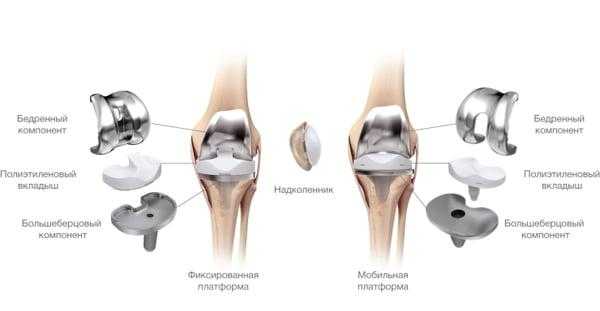

Протезные системы бывают с подвижной или неподвижной платформой, а также предусматривающие сохранение или удаление задней крестообразной связки. Различаются по виду фиксации, она может быть цементной, бесцементной и комбинированной.

- Подвижные и неподвижные платформы. Большинству пациентов ставят имплантат с амортизирующим вкладышем, который плотно связан с большеберцовым элементом, то есть изделия с неподвижной платформой. Наличие же мобильного вкладыша внутри металлического большеберцового компонента требует хорошего состояния мышечной системы и капсульно-связочного аппарата, в противном случае может произойти смещение протеза.

Имплантант позволяет осуществлять движения в двух плоскостях.